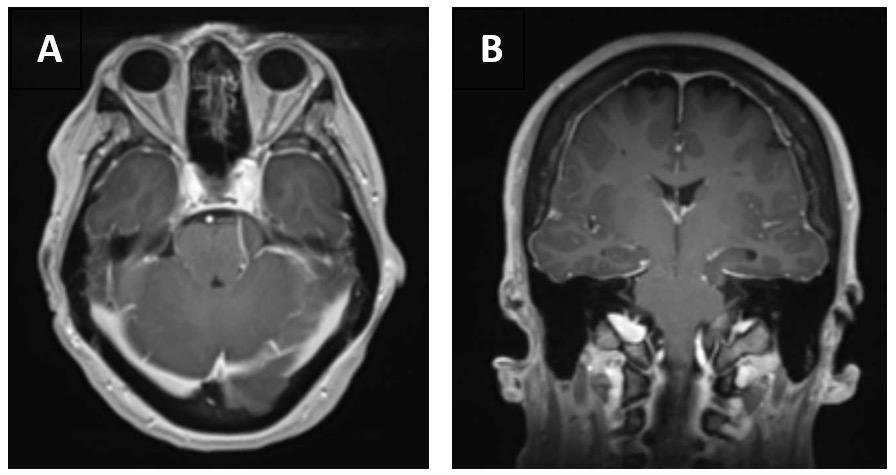

If you like it,why not share it...

Share with a colleague today

Turn static files into dynamic content formats.

Create a flipbook

EMJ 9.4 2024 by European Medical Journal - Issuu